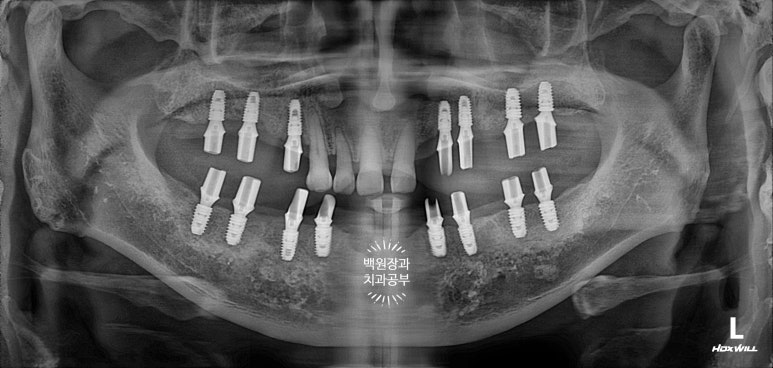

마지막 치과용 파노라마도 촬영해보아야겠죠?

가장 중요한 것은 아주 적절한 위치에 적절한 방향으로 임플란트가 위치하고 있다는 점입니다.

이것이 네비게이션 임플란트의 가장 큰 장점이라고 할 수 있습니다!!!

의료진의 경험을 컴퓨터 기술의 정밀함이 보완함으로써 최상의 결과를 가져오는 치료입니다.